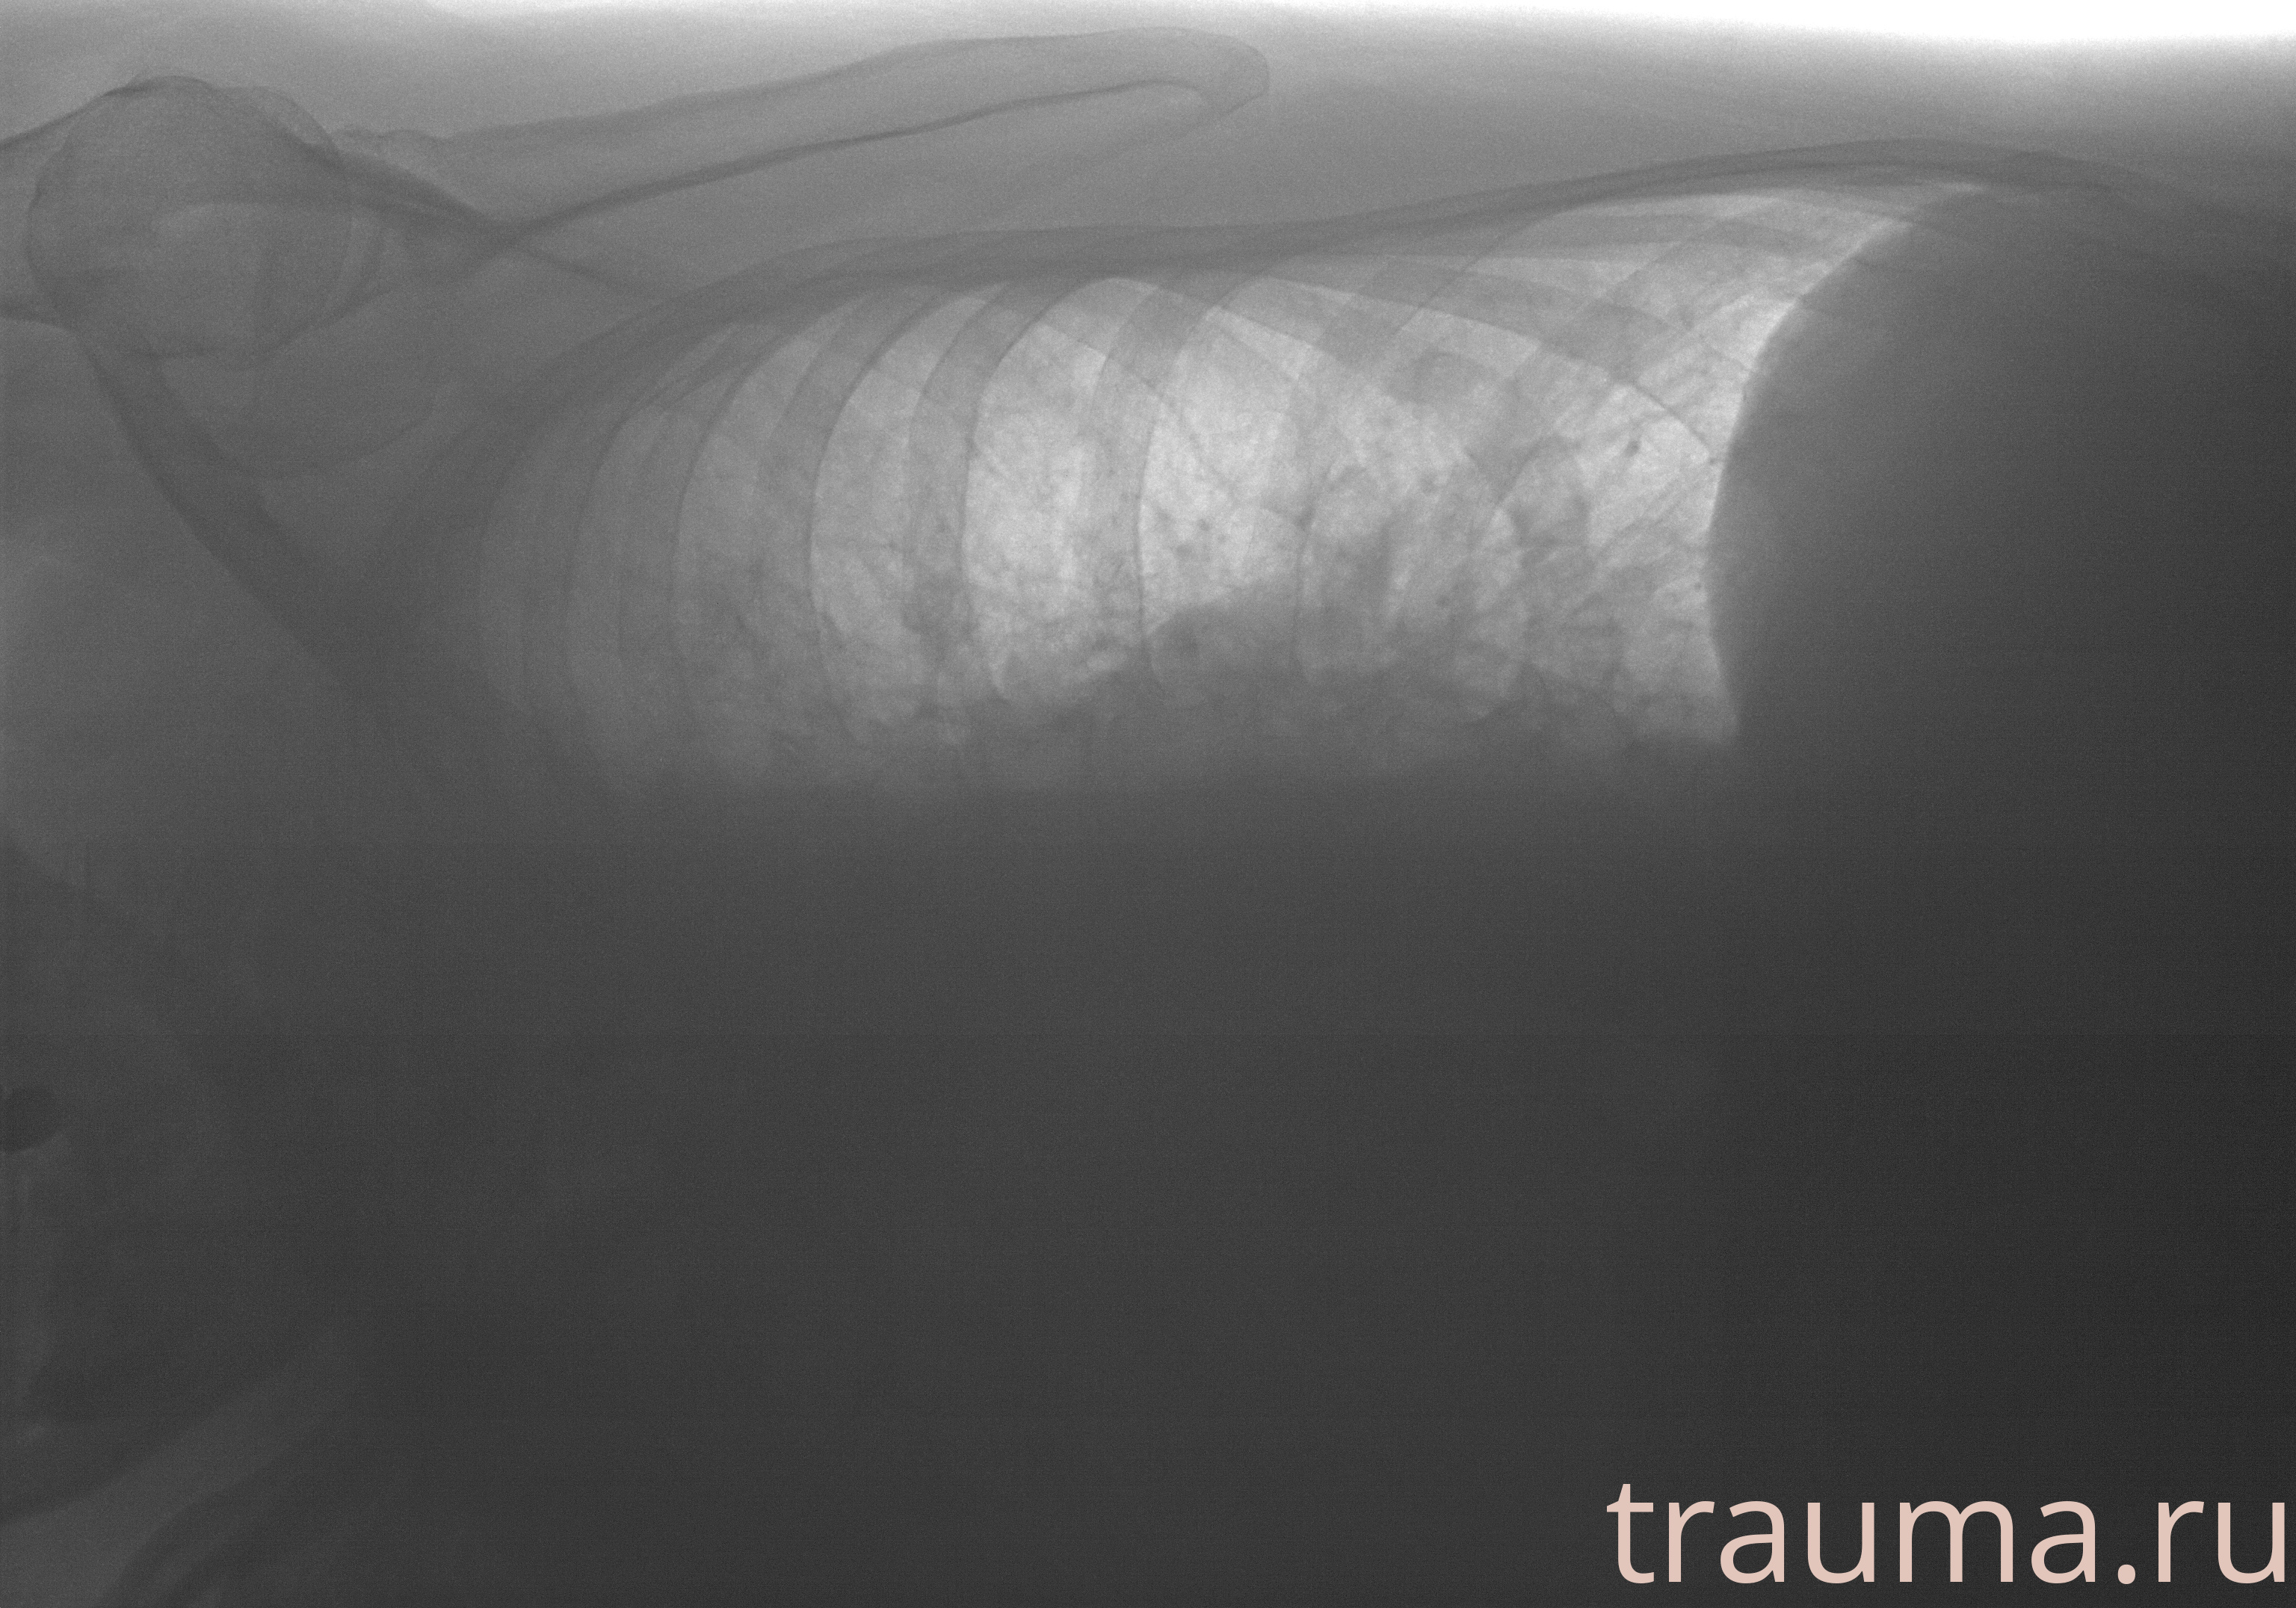

Рентген на дому: по вашему адресу приезжает врач-рентгенолог, травматолог-ортопед с мобильным рентгеновским аппаратом, проводит диагностику травмы или заболевания, делает необходимые рентгенограммы, дает рекомендации по дальнейшему лечению. Получить качественные снимки в домашних условиях возможно благодаря уникальной методике, разработанной МосРентген Центром для института  Склифосовского